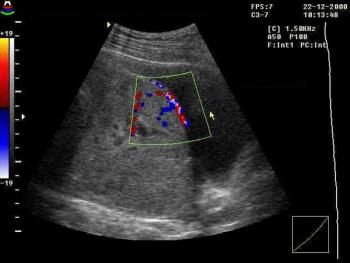

Fibroids are non-cancerous (benign) growths of the muscle wall of the uterus. They are probably responsible for more unnecessary gynecologic surgery than any other condition. It is a staggering number, but about 600,000 American women have a hysterectomy every year. And about 30% of those hysterectomies, 180,000 in all, are performed because of fibroids. For many years these growths have been surgically removed, often because of fear of the problems they might cause in the future. And, those problems are often overstated. While approximately 30% of all women will have fibroids during their lifetimes, the vast majority of these women will never have symptoms and will never require treatment. And, for the rare patient that does have problems, there are a number of sound and effective options available. Hysterectomy should be the solution of last resort.